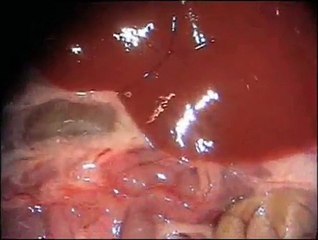

Liver transplantation is surgery to remove a diseased liver and replace it with a healthy liver from an organ donor. A liver transplant is necessary when disease makes the liver stop working. The most common reason for liver transplantation in adults is cirrhosis, a disease in which healthy liver cells are killed and replaced with scar tissue. The most common reason for transplantation in children is biliary atresia, a disease in which the ducts that carry bile out of the liver are missing or damaged. br br We have highly experienced doctors associated with TRANSPLANT COUNSELLOR for liver transplantation.